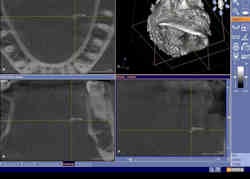

Cone-beam CT dataset showing a 2-mm salivary calculus in the left submandibular gland area in the axial (upper left), coronal (lower left), and sagittal (lower right) view. Clinical and conventional 2D diagnosis failed here due to the small size of the calculus. |

"Even the smallest calculi of 2 mm were visualized with the CBCT datasets," Dr. Dreiseidler stated in an e-mail to DrBicuspid.com. "In fact, standard resolution of CBCT datasets in general is higher than those of medical CT datasets. So, while the smallest voxel of cone-beam CT devices range from 100 to 300 microns, most commonly used medical CT protocols routinely have layer thicknesses of approximately 2 mm." That is why even the smallest salivary calculi can sometimes be depicted even better with cone-beam CT than with medical CT, he noted.